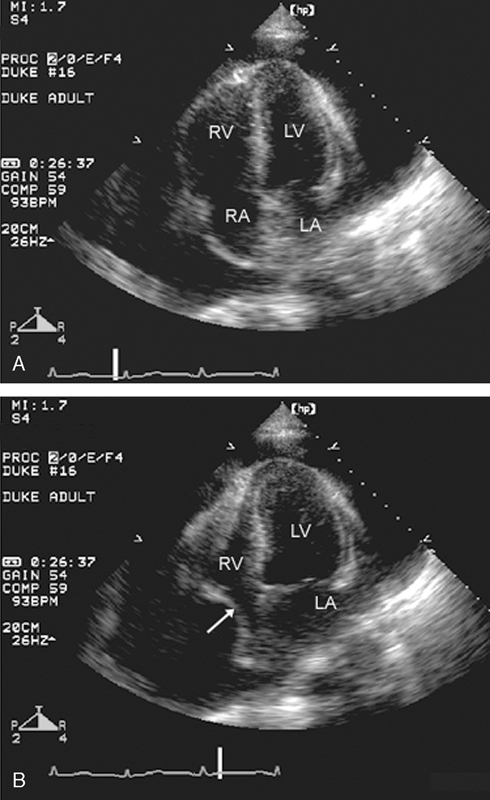

فحوصات تشخيصية لبعض امراض القلب والشرايين التاجية